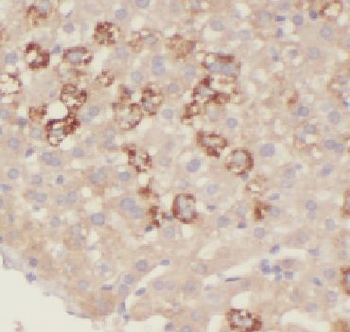

Immunohistochemistry of paraffin-embedded human liver cancer using orb627686 (HIBADH antibody) at dilution of 1:50.